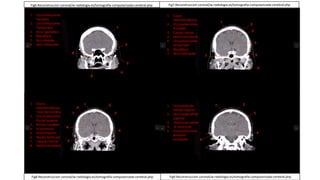

SECUENCIAS ANTERO-POSTERIORES

Fig7.Reconstruccion coronal/w-radiología.es/tomografía-computarizada-cerebral.php

1. Circunvoluciones

frontales

2. Circunvoluciones

Temporales

3. Arco cigomático

4. Mandíbula

5. Arco alveolar

6. Seno esfenoidal

1. Cisura

Interhemisferica

3. Cuerpo calloso

4. Ventrículo lateral

5. Circunvoluciones

6. Mandíbula

7. Seno esfenoidal

/ Hoz del cerebro

frontal superior

3. Núcleo caudado

4. III ventrículo

5. Arteria basilar

6. Núcleo lenticular

7. Capsula interna

8. Ventrículo lateral

1. Circunvolución

2. Seno longitudinal

superior

3. Ventrículo lateral

temporo-

occipitales

Fig6.Reconstruccion coronal/w-radiología.es/tomografía-computarizada-cerebral.php

Fig8.Reconstruccion coronal/w-radiología.es/tomografía-computarizada-cerebral.php Fig9.Reconstruccion coronal/w-radiología.es/tomografía-computarizada-cerebral.php